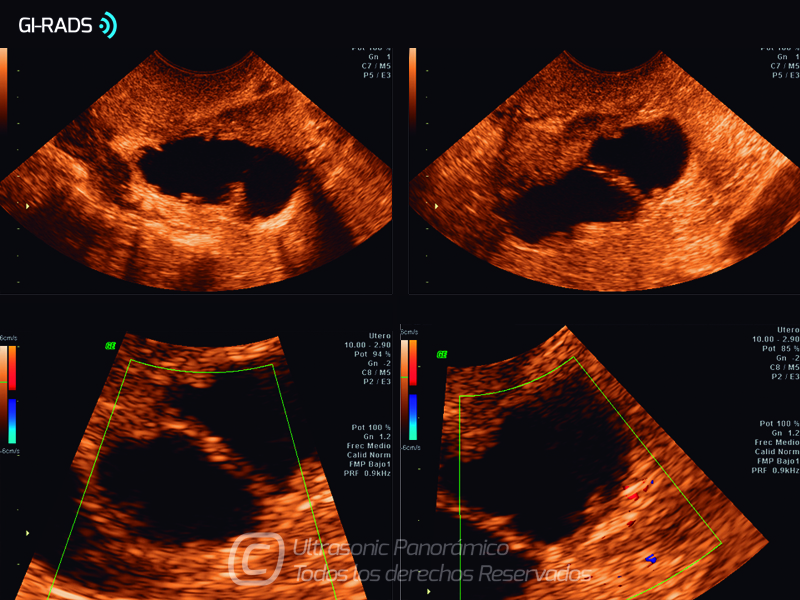

Patologías Benignas – Hidrosalpinx